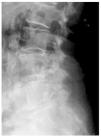

La artrosis interespinosa es una causa poco conocida, aunque no excesivamente rara, de dolor lumbar producida por el desarrollo de una pseudoarticulación entre las apófisis espinosas lumbares. La degeneración o rotura del ligamento interespinoso parece ser un proceso clave en el desarrollo de estos fenómenos degenerativos que pueden acompañarse de la formación de bursas adventiciales. Presentamos el caso de una mujer de 72 años, con antecedentes de cáncer mamario, que presentaba un dolor lumbar crónico y captación en la gammagrafía ósea en la zona de las apófisis espinosas de L4-L5. Las pruebas radiológicas efectuadas demostraron una artrosis interespinosa (síndrome de Baastrup) asociada a una degeneración avanzada del ligamento interespinoso, efectuándose tratamiento conservador con control del dolor lumbar hasta el momento.

Interspinous osteoarthritis is not rare but it is often an unrecognised cause of lumbar pain produced by pseudoarthrosis between lumbar spinous apophysis. Degeneration and/or rupture of interspinous ligament is the key problem of this degenerative process that may promote development of adventitial bursas. We present the case of a 72 years-old woman with history of breast cancer since 4 years that presented with chronic low back pain and markedly increased activity at L4 and L5 spinous processes at bone scintigraphy. A radiological diagnosis of interspinous osteoarthritis (Baastrup syndrome) with severely degenerated interspinous ligament was made. The back ache has been relieved partially with conservative treatment until this moment.